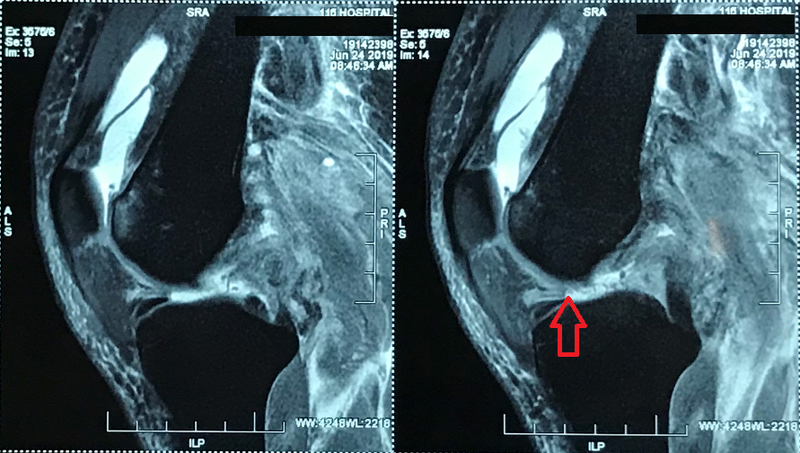

Tại Khoa Điều trị theo yêu cầu – Y học thể thao của Bệnh viện, kết quả chụp MRI khớp gối trái cho thấy, bệnh nhân đứt hoàn toàn đoạn gần dây chằng chéo trước, đứt hoàn toàn đoạn gần dây chằng chéo sau, đứt hoàn toàn đoạn gần dây chằng bên bên ngoài và bong gân độ I dây chằng bên bên trong.

Bị đứt nhiều dây chằng khớp gối trái như vậy là một trong những tổn thương nặng nề nhất ở khớp gối.

Hình ảnh bị đứt nhiều dây chằng khớp gối trái của bệnh nhân trước khi mổ